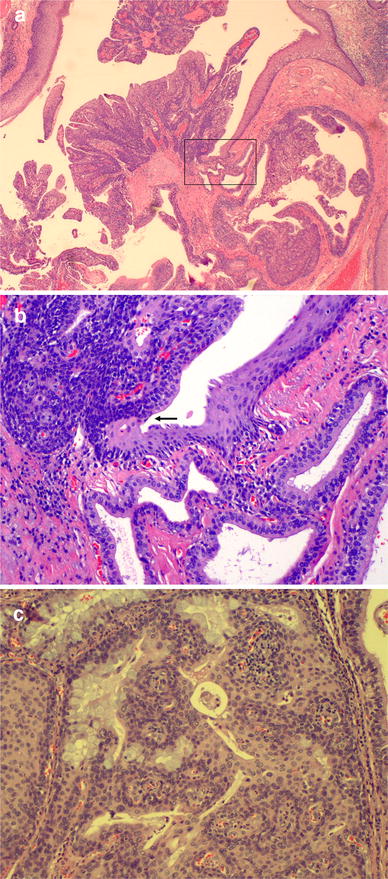

Microscopically, the lesion demonstrates prominent papillarity that in some areas, appears to be centered around an excretory minor salivary gland duct. The opening of the duct is in direct continuity with the stratified acanthotic squamous epithelium covering the papillary areas of the tumor (Fig. 1a, b). Most of the ductal epithelium is bi-layered or stratified with tall columnar cells in the luminal layer and short, cuboidal cells in the basal layer. Scattered goblet cells and ciliated metaplastic cells are interspersed. Extensive squamous metaplasia is present focally. The papillary fronds of the tumor, which are supported by fibrovascular cores, protrude into the ductal space. Lymphocytic and plasmacytic inflammation is present in the cores. The above described lesion was interpreted as sialadenoma papilliferum.

Fig. 1

a Sialadenoma papilliferum. Exophytic portion. 20×; hemotoxylin-eosin stain. Boxed area is shown in higher magnification in illustration b. b Excretory salivary duct in direct connection with squamous epithelium. Arrow indicates the connection between squamous surface epithelium and salivary excretory duct columnar epithelium. 200×; hemotoxylin-eosin stain. c Mucoepidermoid carcinoma with intermixed components of squamoid, mucous and intermediate cells. 200×; hemotoxylin-eosin stain